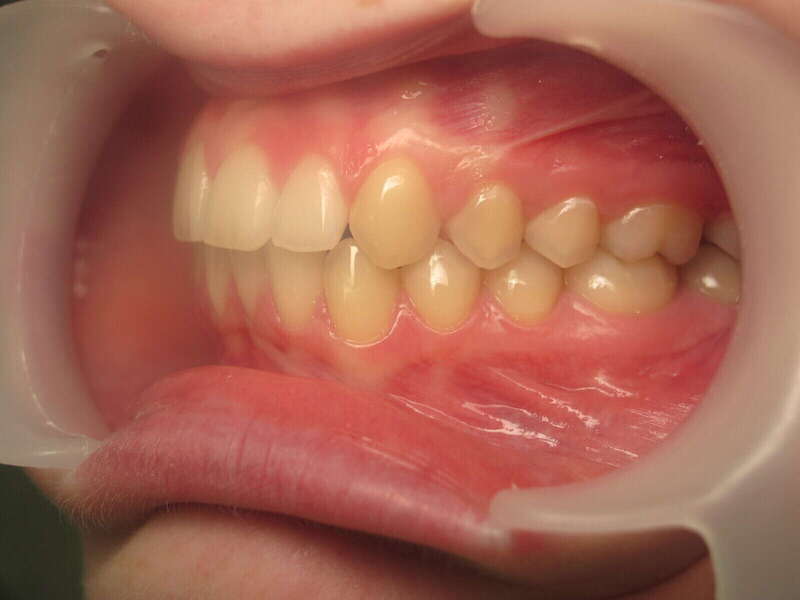

Cas n°1 traité par aligneurs - adolescent

Ce cas d’une adolescente illustre la correction d'une Classe II avec supraclusion par aligneurs. La stratégie thérapeutique a reposé sur une distalisation séquentielle de l'arcade supérieure. Ce mouvement précis a permis de reculer les dents maxillaires étape par étape pour annuler le surplomb (overjet) sans extractions.

Résultats clés :

• Correction fonctionnelle : Retour à un engrènement de Classe I stable et correction du recouvrement vertical.

• Esthétique restaurée : Harmonisation globale du sourire et du profil.

• Approche moderne : Un traitement discret, confortable et hautement prévisible.

Le résultat final montre une occlusion saine et un sourire parfaitement aligné, garantissant une santé dentaire et articulaire optimale pour l'avenir.

Avant

Après